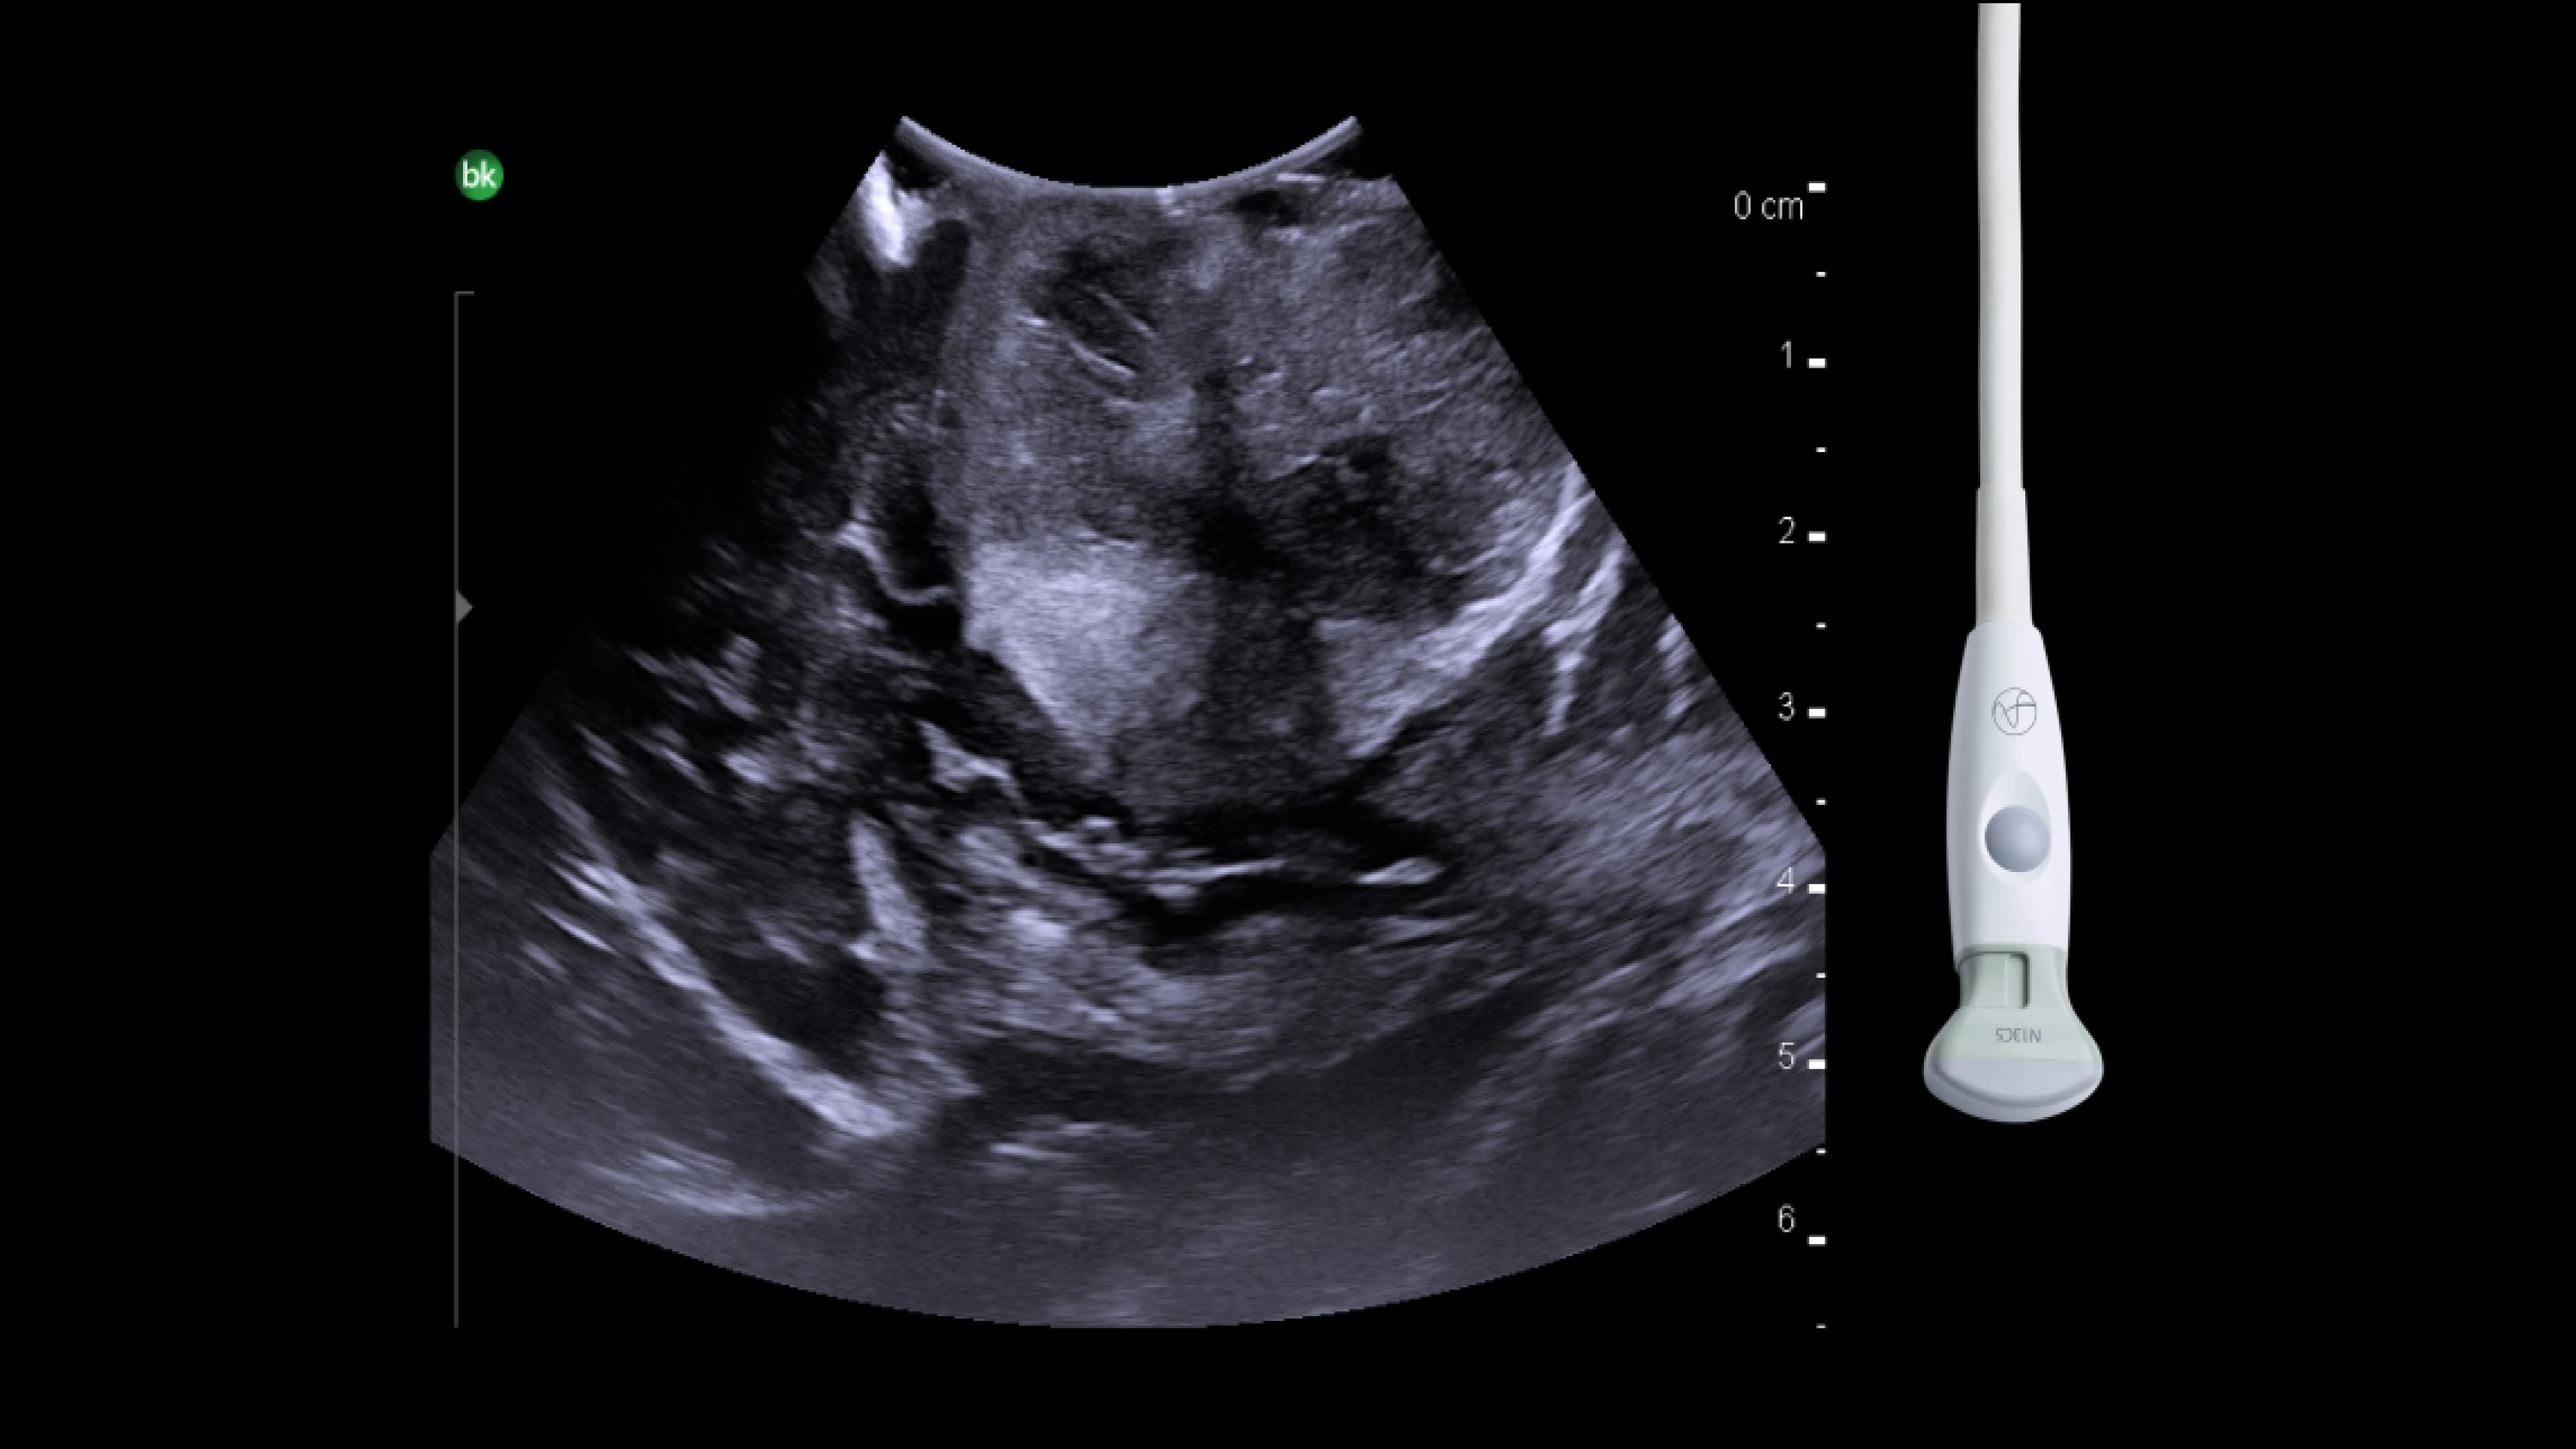

Spine

Visualize soft tissue in detail with Active Imaging. Active imaging offers real-time guidance in a variety of spinal procedures during open and minimally invasive approaches: spinal decompressions, chiari malformations, tumor resections, selective dorsal rhizotomy, anterior cervical discectomy and fusion.